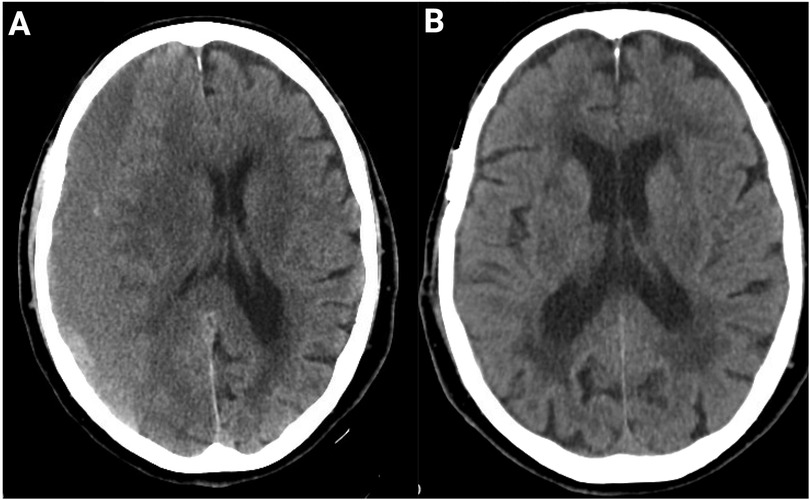

Chronic subdural hematoma (cSDH) is one of the most common neurosurgical conditions, with incidence expected to rise sharply as populations age. Once regarded as a passive sequela of venous rupture, cSDH is now understood as an active, membrane-driven disorder characterized by persistent inflammation, fragile neovascularization, and local fibrinolysis that collectively fuel hematoma expansion and recurrence. This evolving biological model explains the limitations of traditional surgical approaches, which relieve mass effect but do not address the underlying pathophysiology. Burr-hole drainage with subdural drainage remains the gold standard, though recurrence rates approach 10–20% and perioperative risks are magnified in frail patients. Minimally invasive strategies, such as twist-drill craniotomy and the subdural evacuating port system, expand options for high-risk populations, while mini-craniotomy may benefit complex or organized collections. Emerging adjuvant therapies, including middle meningeal artery embolization, statins, tranexamic acid, and corticosteroids, target the inflammatory and angiogenic milieu; however, results remain heterogeneous, and safety concerns persist. Novel directions such as biomarker-guided patient stratification, anti-VEGF therapies, platelet-rich plasma injection, and endoscopic membranectomy reflect a paradigm shift toward disease-modifying interventions. Collectively, these advances highlight a growing opportunity to personalize treatment, reduce recurrence, and improve long-term outcomes in cSDH.